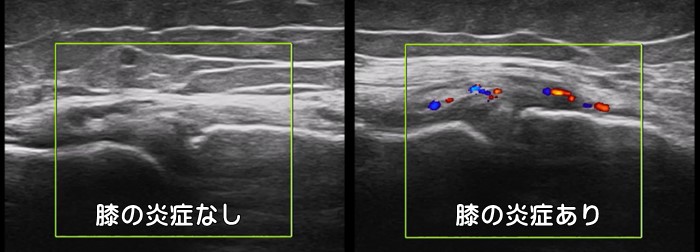

膝関節の炎症

エコー検査では膝関節の炎症もパワードプラと呼ばれる機能を使い確認可能です。

炎症が起こっていると本来は無いはずの異常な血管が赤く描出されます。